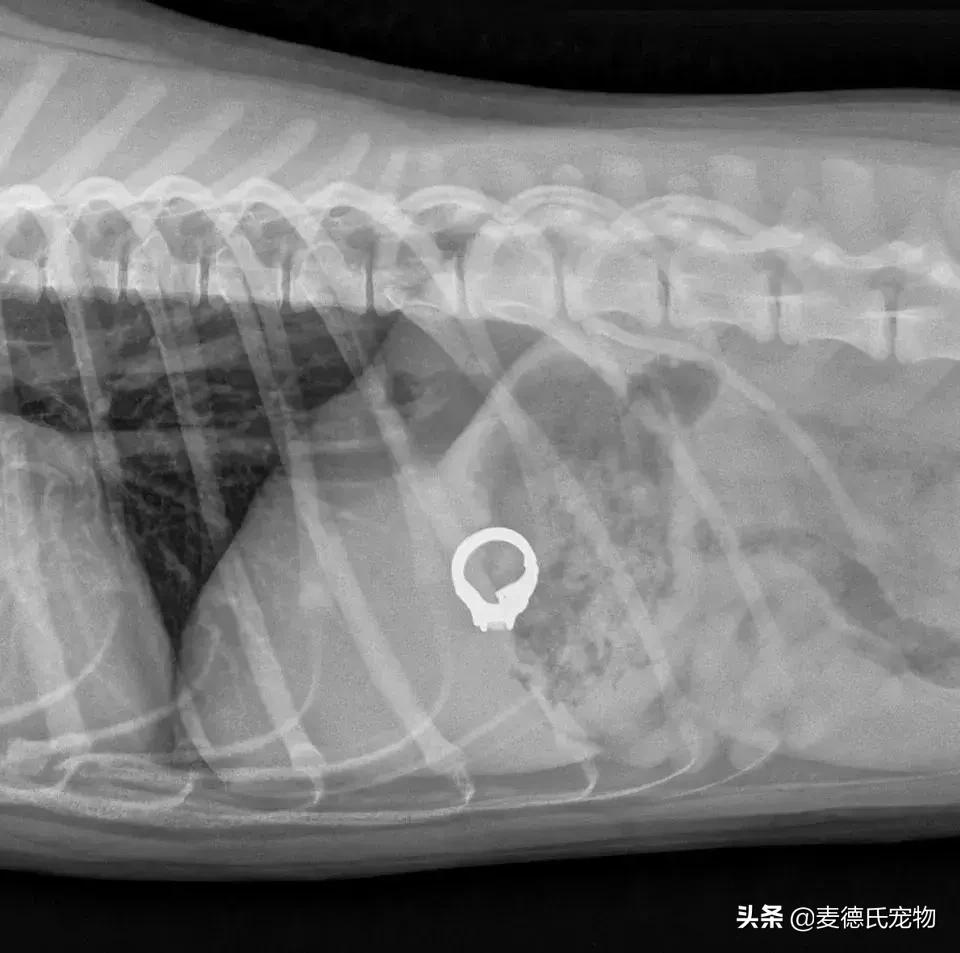

一铲屎官最爱的订婚戒指不见了,到处寻找一无所获后,她特地借来了一个金属探测仪,开始在家里地毯式的排查...

最后还是无意间发现,用金属探测仪靠近她家其中一只狗狗时,仪器就会响...

铲屎官连忙送狗狗去了医院,拍片后发现,戒指还真在这货肚子里!

还好后来经过诱吐的方式才成功拿回了戒指,而狗狗也没受多大罪...